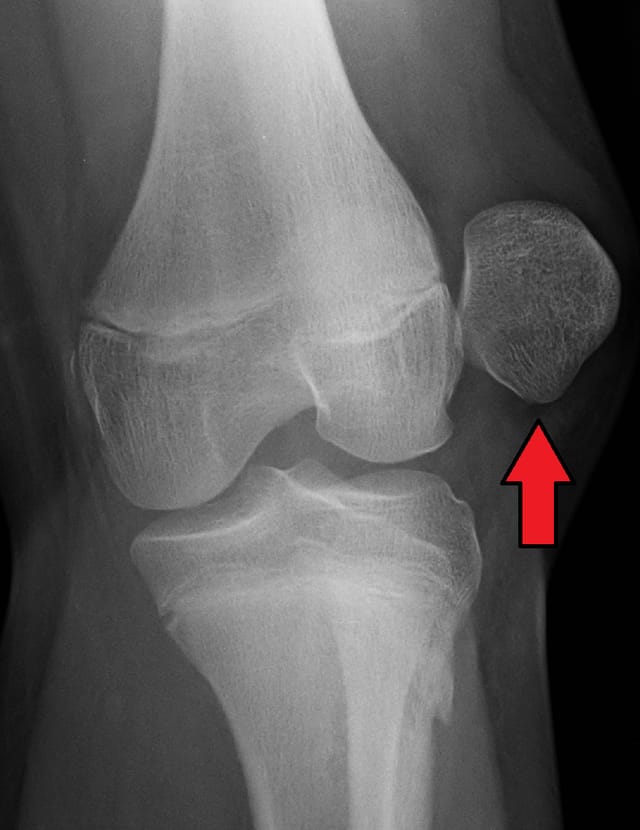

The patella is dislocated laterally, it should be in the center of the knee